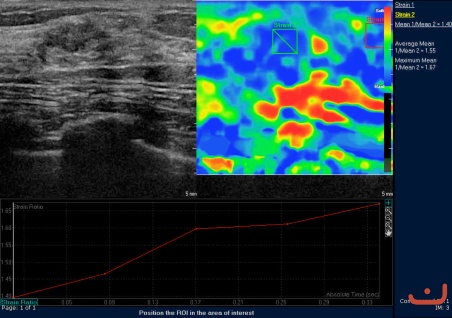

Case 63-E1

Benign solid mass

Friday, 22 May 2015

136.30 KB (452 x 318 px)